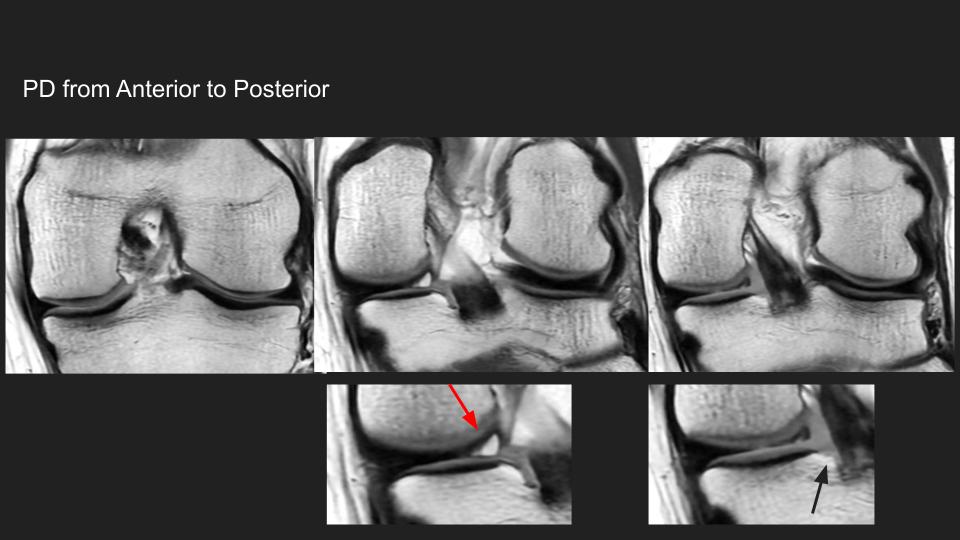

63F 2 weeks after knee twisting injury with pop MRI, question about AMRI

I realize I didn’t attach the reference I found (now that Diego Lemos just shared it with me) https://www.ncbi.nlm.nih.gov/pmc/articles/PMC6925612/ They have a section focusing on AMRI….curiously, the reference that focuses on meniscal root tear only mention posterior Lateral meniscal root tear (in the title) The body of the discussion does not provide any details, just […]